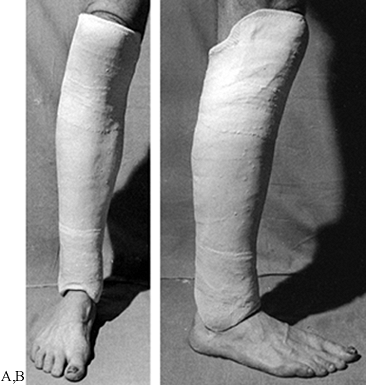

![]() |

|

Figure 10.40. Completed Sarmiento short-leg weight-bearing cast. A:

Frontal view. Notice the contouring of the cast to the anatomy of the leg, the flat molded surfaces over the subcutaneous borders of the tibia and anterior compartment, and the spacious fit around the toes. B: Side view. Notice that the cast has been flattened over the upper gastrocsoleus area to push the tibia forward in the cast. This increases containment and improves the hydraulic support for the fracture. C: My modification of the trimming of the upper end of Sarmiento’s cast. |